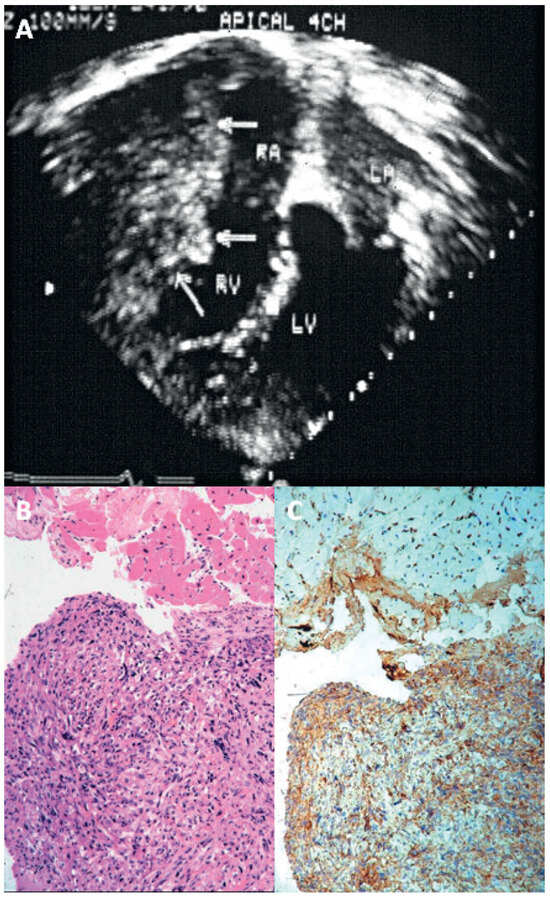

- Poletti, A.; Cocco, P.; Valente, M.; Fasoli, G.; Chioin, R.; Thiene, G. In vivo diagnosis of cardiac angiosarcoma by endomyocardial biopsy. Cardiovasc Pathol. 1993, 2, 89–91. [Google Scholar] [CrossRef] [PubMed]

- Basso, C.; Stefani, A.; Calabrese, F.; Fasoli, G.; Valente, M. Primary atrial fibrosarcoma diagnosed by endocardial biopsy. Am Heart J. 1996, 131, 399–402. [Google Scholar] [CrossRef] [PubMed]